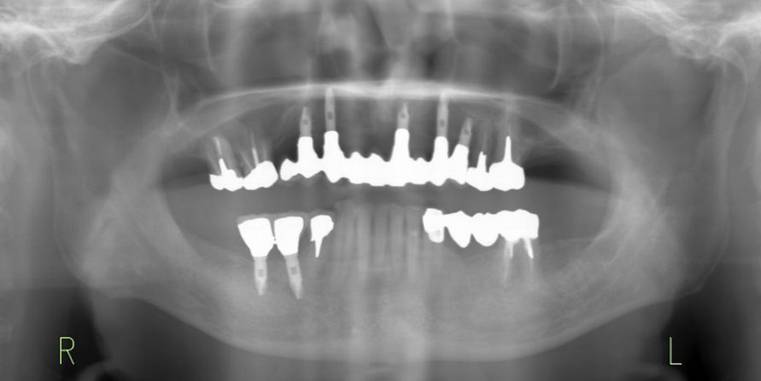

治療後。歯周病で失われた骨が回復しています。使用インプラントはスプラインツイストです。

術後。上部構造はハイブリッドレジンです。しっかり嚙めるようになり喜んでいただきました。

上顎

下顎